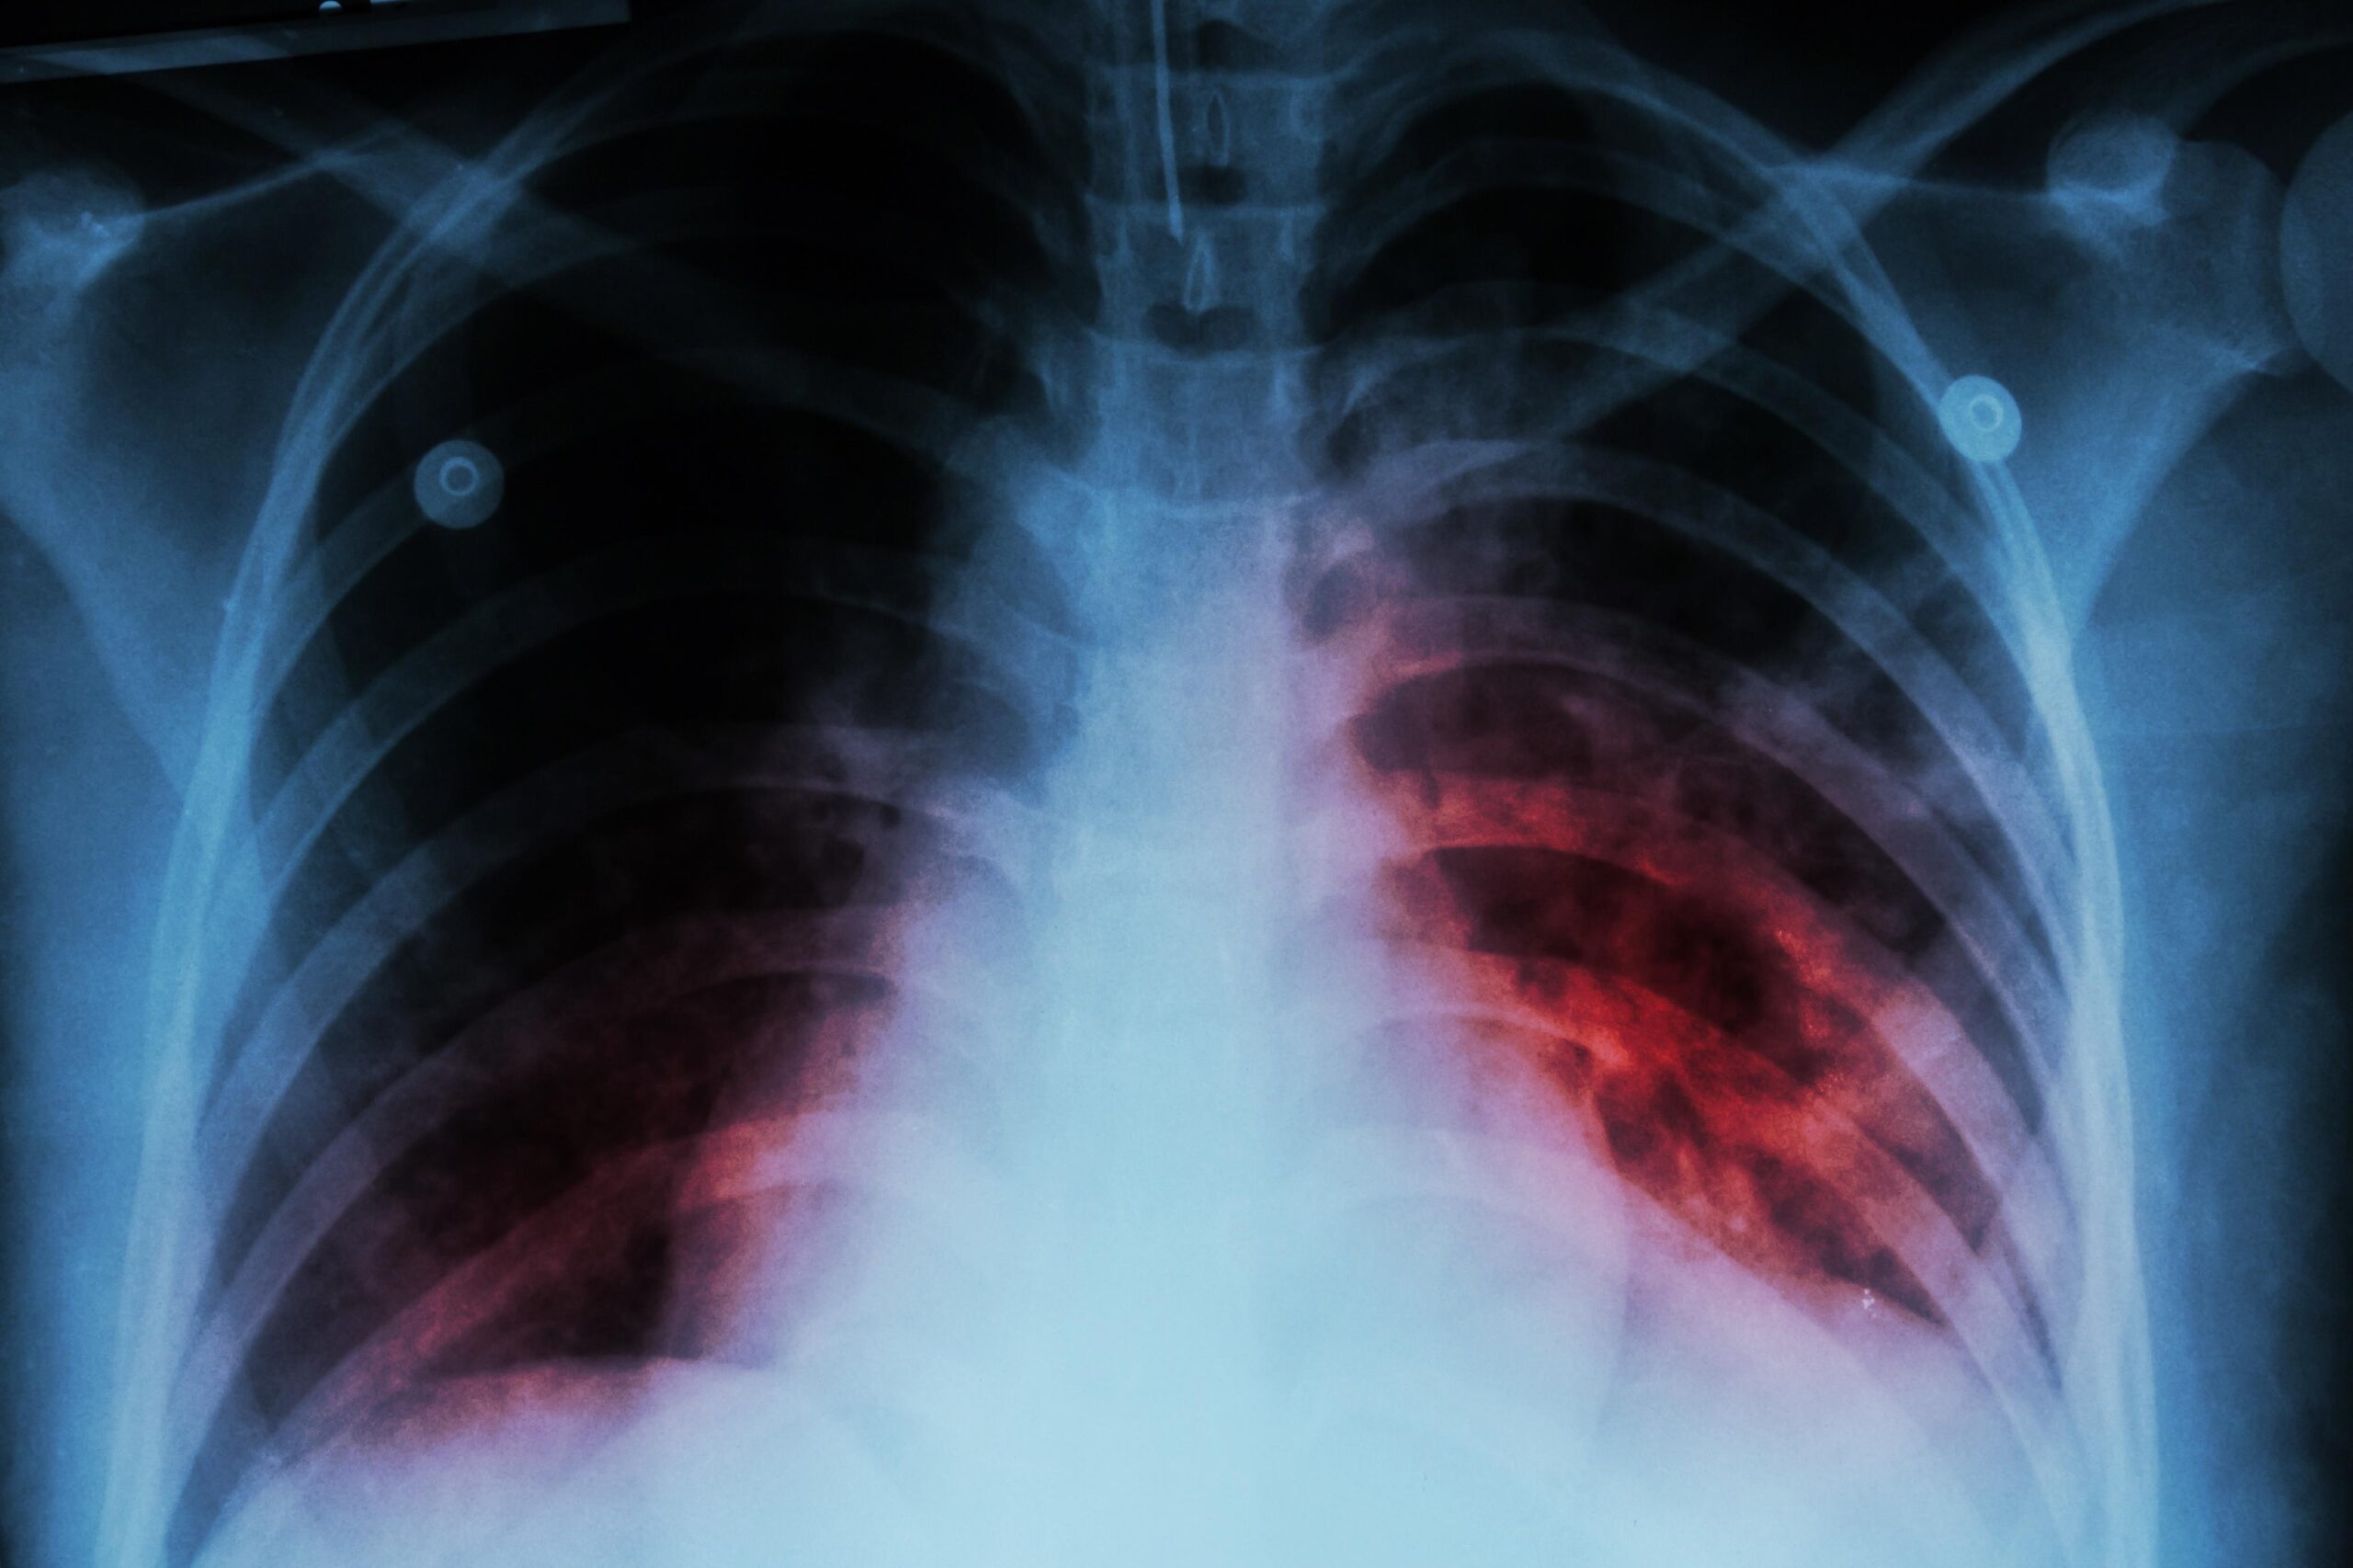

La radiografía de tórax es esencial en la valoración de la tuberculosis pulmonar. Suele mostrar lesiones apicales, cavitaciones, infiltrados en segmentos posteriores y otras alteraciones sugerentes. En casos complejos, se recurre a tomografía computarizada, resonancia magnética (sobre todo en afectación neurológica) o ecografía (para pleura, ganglios o abdomen). Además, en todo paciente diagnosticado de tuberculosis se recomienda ofrecer prueba de VIH, dado el fuerte vínculo entre ambas infecciones.